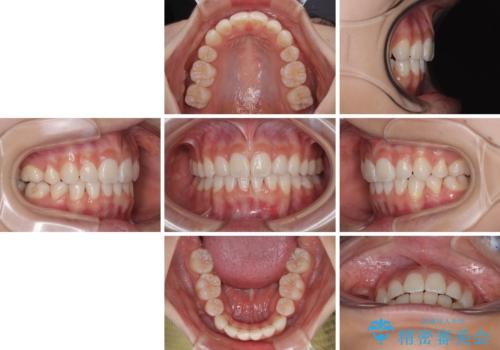

下唇に前歯が当たって跡が残ってしまう状態でしたが、スッキリとした口元に仕上げることができました。